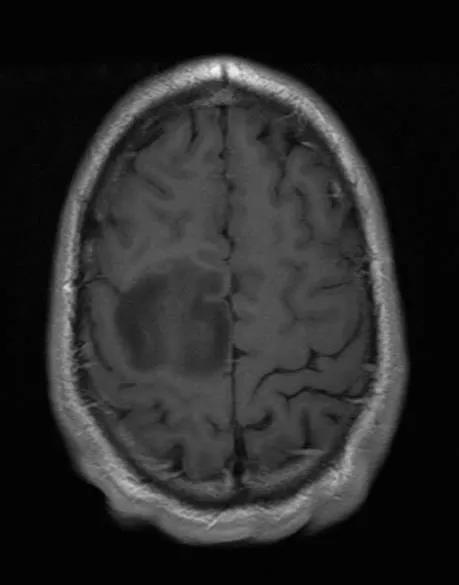

En MR-scanner kan lave et detaljeret billede af kroppens indre ved hjælp af et kraftigt magnetfelt, som registreres af en computer. Magnetfeltet er så kraftigt, at du ikke må have metaldele i kroppen. Det gælder dog ikke plomber i tænderne.

En MR-scanning viser betydeligt flere detaljer end CT-scanning, og hjernen kan ses fra alle vinkler ved denne undersøgelse. Læs mere om undersøgelsen:

Scanningsbilledet kan være en god hjælp til at forstå sin sygdom. Nogle patienter får et enkelt epileptisk anfald som det første symptom, og de kan have svært ved at tro på, at de har en hjernetumor.